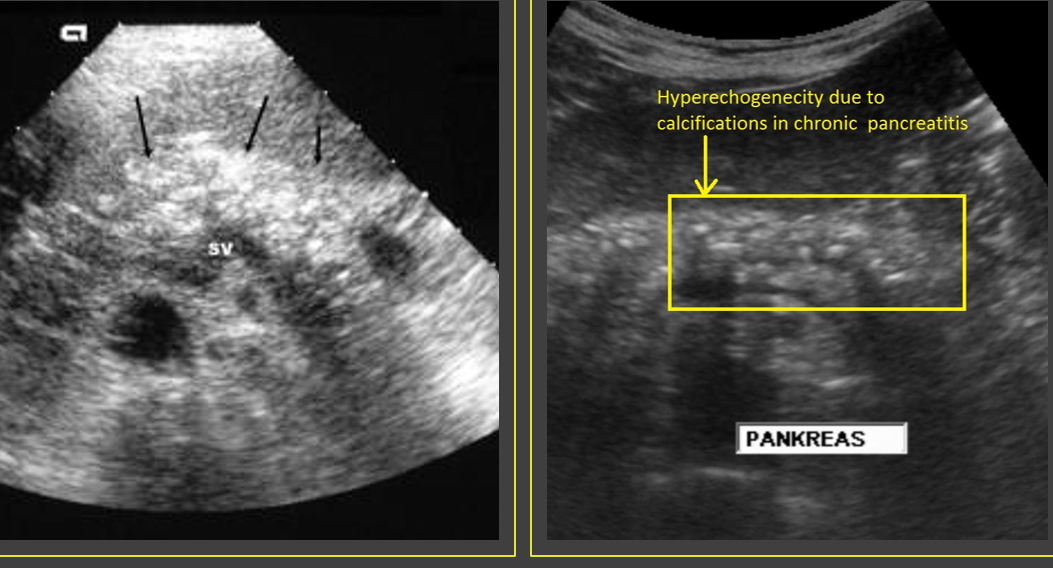

Chronic pancreatitis results from _____ attacks of ____ pancreatitis and causes continuous ______ of the pancreatic parenchyma

recurrent; acute; destruction

Patients with chronic pancreatitis may be _______

asymptomatic

Clinical findings of chronic pancreatitis include _______ pain radiating to the back and _______

epigastric; nv

Chronic pancreatitis is generally associated with chronic _______ or ______ disease

alcoholism; biliary

Sonographically, chronic pancreatitis may appear _____ or ______ with increased ______, size _____, ______ borders, and ______ duct

localized; diffuse; echogenicity; reduced; irregular; dilated

What is a classic finding of chronic pancreatits?

Calcification